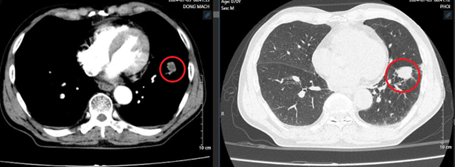

Chụp cộng hưởng từ sọ não: Nhu mô não vùng trên lều tiểu não có các nốt tổn thương nhu mô não dưới vỏ thuỳ trán trái, thùy đỉnh hai bên và thùy chẩm phải, đường kính ổ tổn thương lớn nhất 12mm, ngấm thuốc mạnh sau tiêm, có phù não rộng xung quanh.

Hình 2: Hình ảnh cộng hưởng từ sọ não: Các nốt tổn thương nhu mô não ngấm thuốc mạnh sau tiêm, có phù não rộng xung quanh (vòng tròn màu đỏ)(B: Thùy chẩm, A,C: Thùy đỉnh)

Nhận xét: Trước điều trị hóa chất xuất hiện hình ảnh nhu mô não có các nốt tổn thương nhu mô não hai bên ngấm thuốc mạnh sau tiêm, có phù não rộng xung quanh, tuy nhiên sau điều trị hóa chất 3 chu kỳ, không còn thấy hình ảnh tổn thương thứ phát tại não.